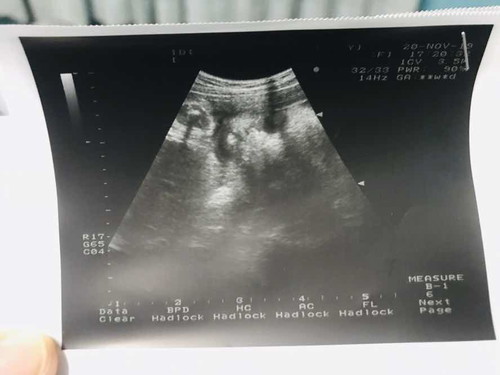

ท้องแฝด

ตอนนี้ตั้งครรภ์ได้ 34 สัปดาห์ 3 วัน ท้องแฝด ผู้ชายทั้งคู่ น้ำหนัก 1950 กรัม กับ 1920 กรัม น้ำหนักขึ้นมา 14 โล ปกติของเด็กแฝดช่วง 8 เดือนเข้า 9 เดือน น้ำหนักจะอยู่ที่เท่าไรคะ...